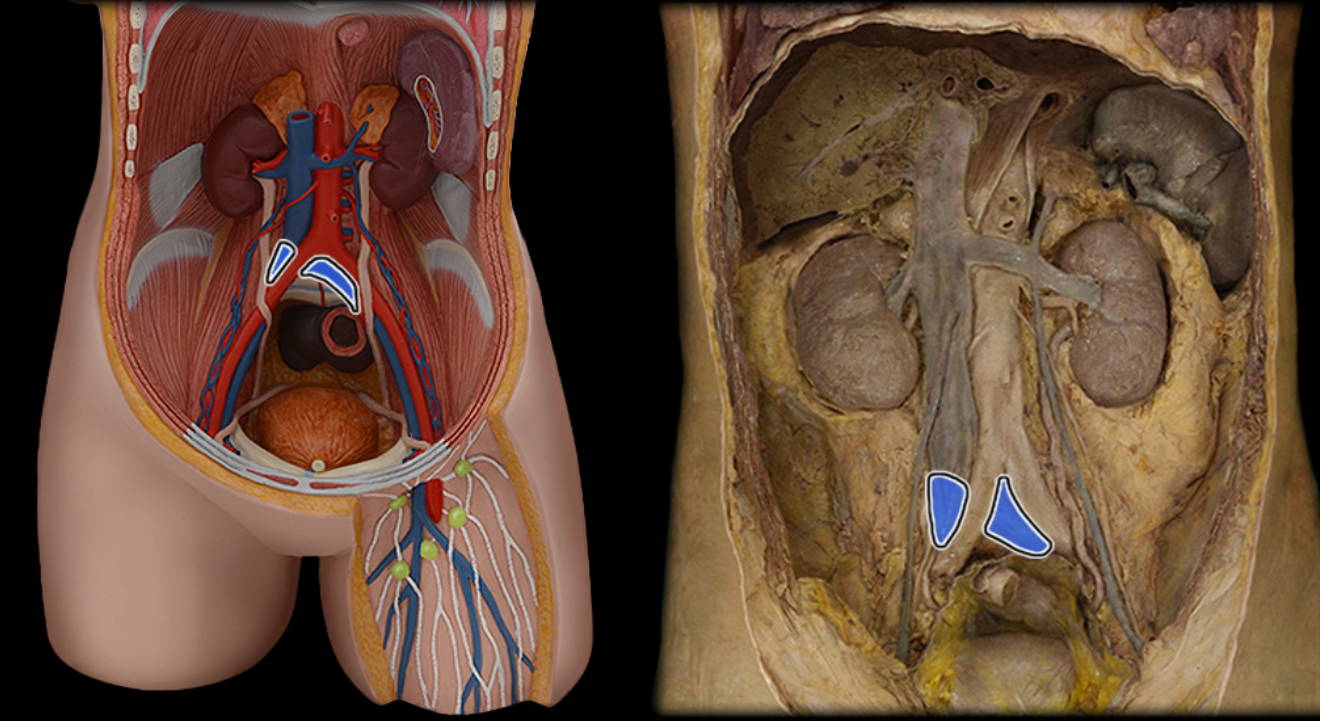

Abdominal aorta

Common iliac a.

Common iliac v.

External iliac a.

External iliac v.

Inferior vena cava